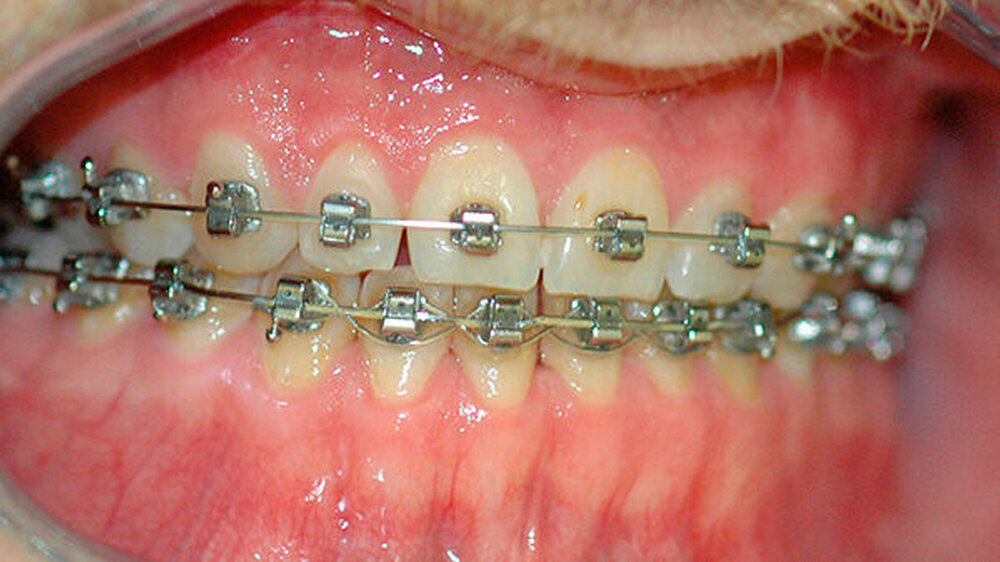

Die Abbildungen 1 und 2 zeigen die klinische Situation bei Erstvorstellung: Der Unterkiefer ist zu prominent. Der Oberkiefer und das Mittelgesicht liegen zurück. In der Front liegt ein umgekehrter Überbiss vor. Der Unterkiefer steht vor dem Oberkiefer. Das erschwert das Abbeißen und Kauen der Nahrung. Die Scans (siehe Abbildungen) dokumentieren, wie aufwendig die virtuelle Operationsplanung erfolgen musste.